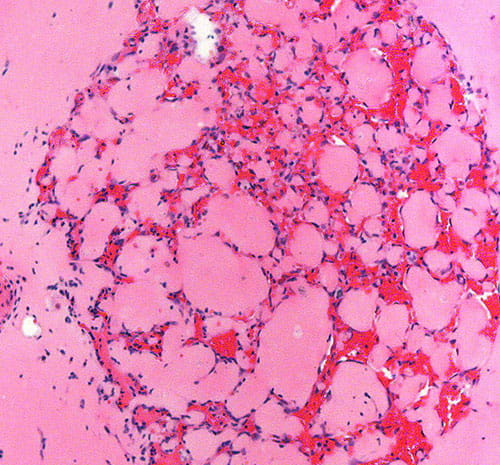

1) Diagnostic biomarker identification and analysis for vascular anomalies

2) Human patient-derived cell xenograft models of vascular anomalies

3) Mouse models of vascular anomalies

“Pathogenesis and Treatment of Kaposiform Lymphangiomatosis“

The major goals of this project are to test the hypothesis that the somatic p.Q61R NRAS mutation in human endothelial cells drives the pathogenesis of KLA and elevated production of ANGPT2.